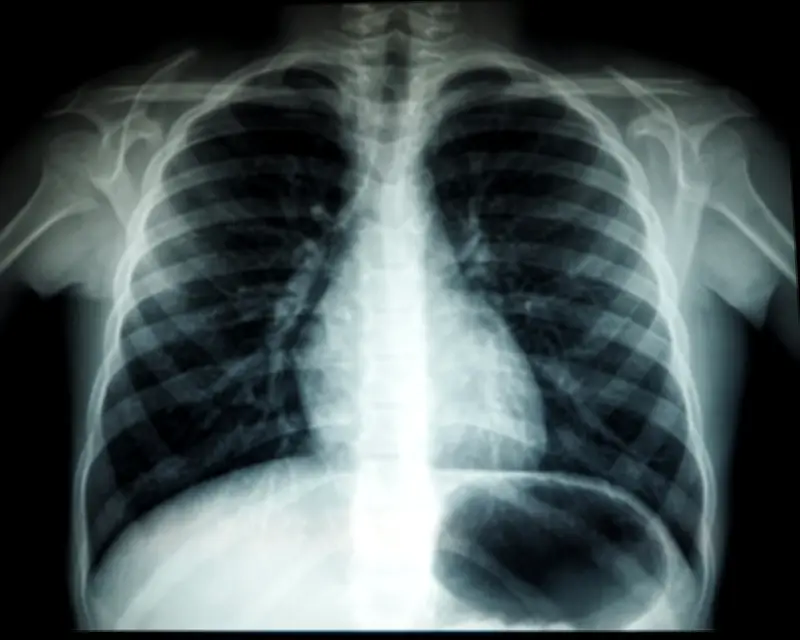

Dr Amirul Syafiq Hishamudin, pengasas bersama Klinik Perubatan Jauhar (JMC), menjelaskan bahawa TB adalah penyakit berjangkit berbahaya yang disebabkan oleh bakteria Mycobacterium tuberculosis. Bakteria ini biasanya menyerang paru-paru (TB pulmonari) tetapi boleh merebak ke organ lain seperti tulang, usus, dan nodus limfa.

"Jangan panik kerana penyakit ini boleh dirawat jika tindakan awal diambil. Jalani pemeriksaan kesihatan berkala, termasuk ujian darah dan X-ray dada, dan dapatkan perundingan segera jika ada gejala TB atau mempunyai kontak rapat, terutamanya jika batuk berlanjutan lebih dua minggu," tambahnya.